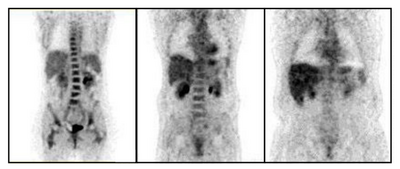

- Heavy patient problem: The quality of the PET images decreases with increasing weight of the patient due to increased attenuation (Figure 10) [11].